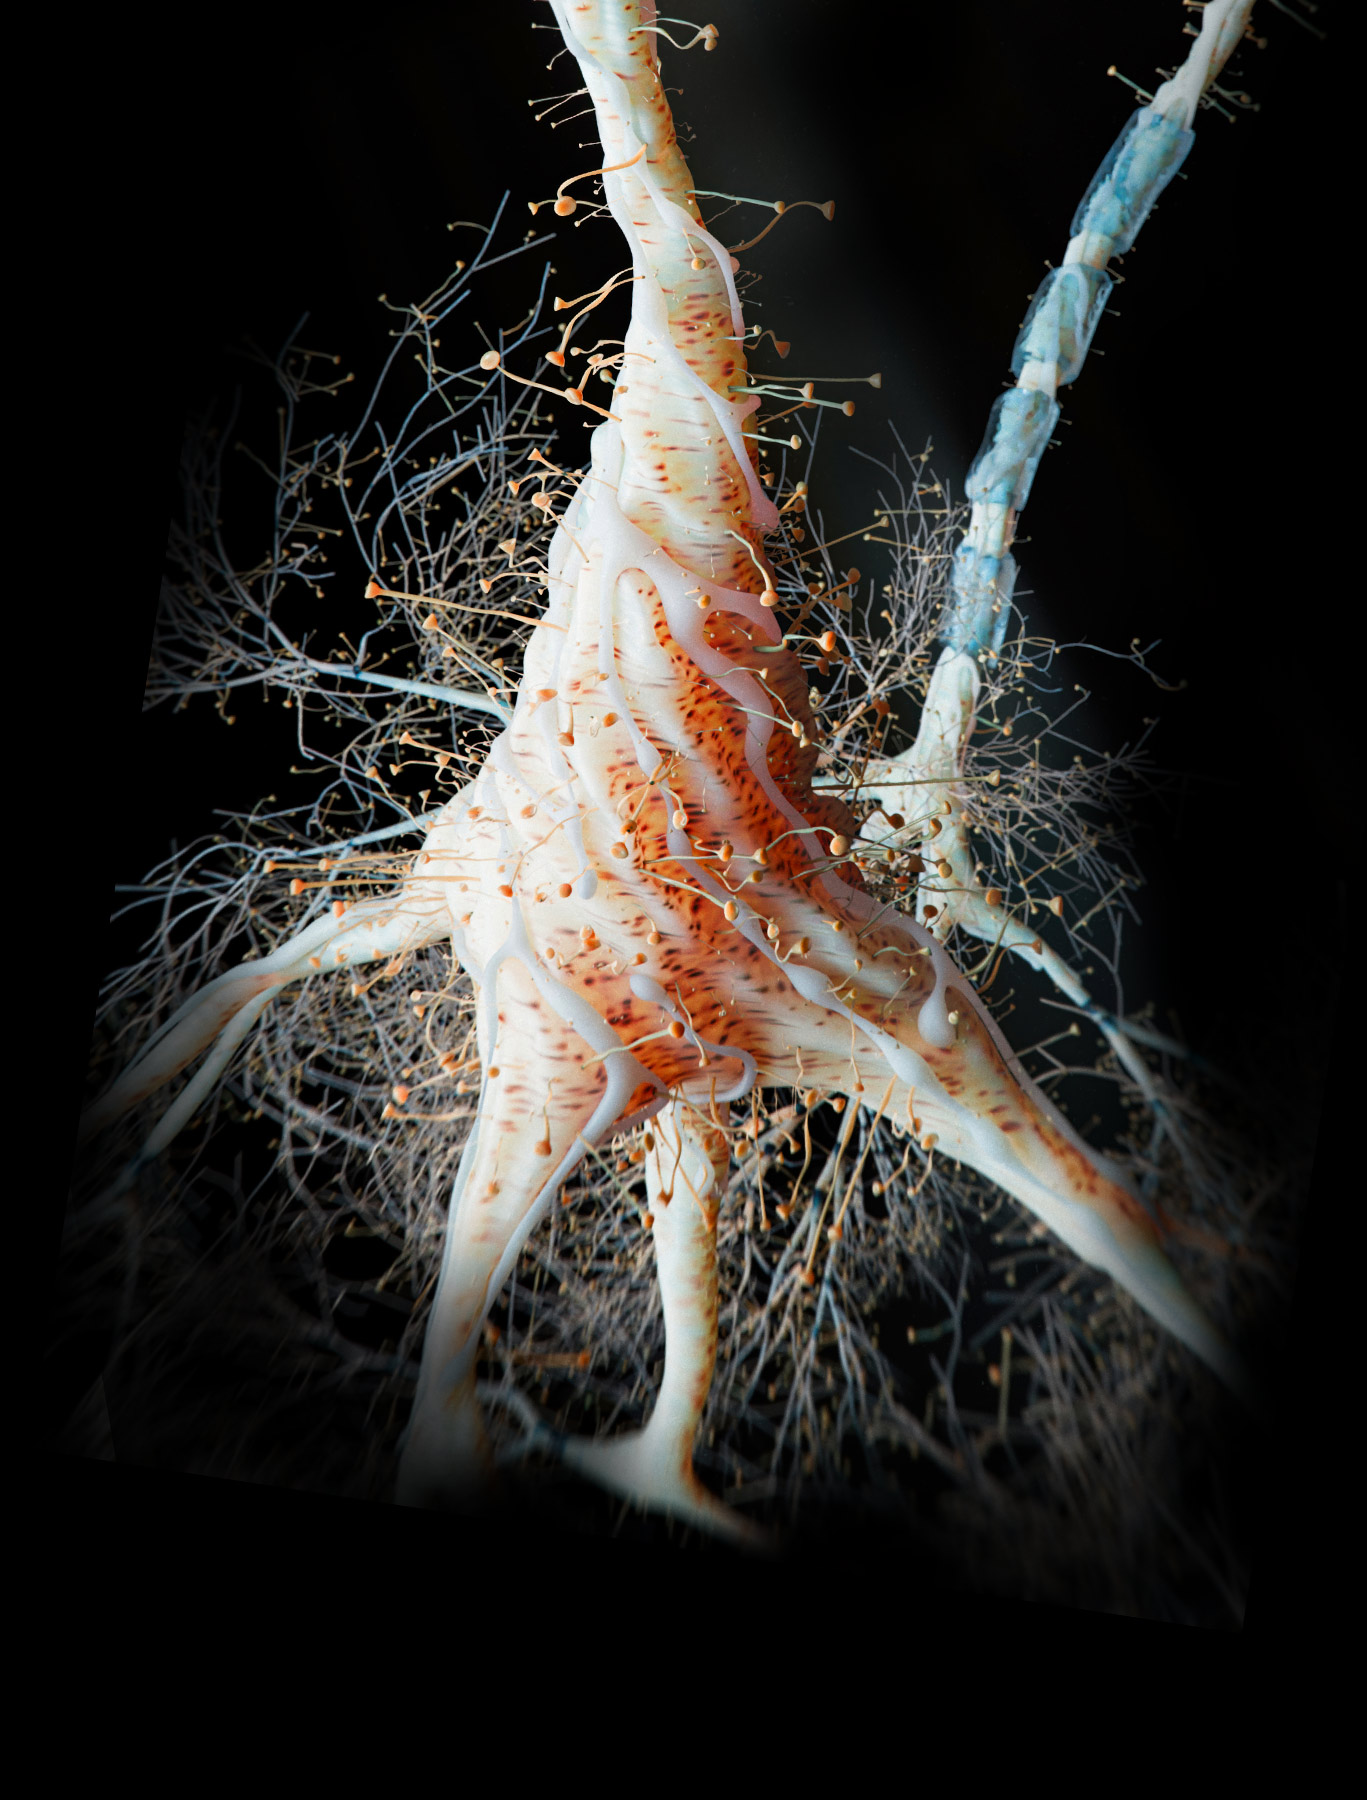

Phosphatidylserine (from sunflower lecithin) is a phospholipid from sunflower lecithin, and brain-essential nutrient. It is a major phospholipid in the brain, supporting healthy membrane and neurotransmitter signaling, especially in parts of the brain related to memory functions.*

Acetyl-L-Carnitine HCl: an acetylated form of L-carnitine. This form of carnitine crosses the blood-brain barrier and is the preferred form for use in brain and nervous system support. It supplies carnitine and acetyl groups that collectively support the healthy production of acetylcholine neurotransmitter molecules, brain energy production, and neuroprotective functions.*

L-alpha-Glycerylphosphorylcholine (alpha GPC): a choline form found in the brain. It supports healthy acetylcholine production, an important neurotransmitter involved in attention, concentration, learning, memory, and neuroplasticity. Alpha GPC also supports phospholipid metabolism in the brain, which is important for keeping brain cells healthy.*

L-alpha-Glycerylphosphorylcholine (alpha GPC): a choline form found in the brain. It supports healthy acetylcholine production, an important neurotransmitter involved in attention, concentration, learning, memory, and neuroplasticity. Alpha GPC also supports phospholipid metabolism in the brain, which is important for keeping brain cells healthy.*